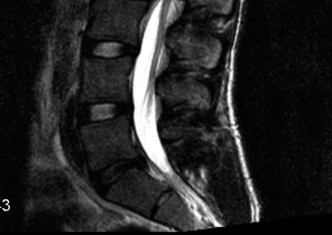

Magnetic Resonance Imaging and the Posterior Ligamentous Complex

To definitively assess the integrity of the soft tissue stabilizers and the neural elements, a Magnetic Resonance Imaging (MRI) scan without contrast was performed. Historically, textbooks propagated the "50-50-25 rule," suggesting that a burst fracture was inherently unstable if it exhibited >50% canal compromise, >50% loss of vertebral body height, or >25 degrees of kyphosis. Modern spine trauma surgery has largely debunked this rigid radiographic dogma. We now understand that these bony metrics alone do not dictate mechanical instability. The true arbiter of stability is the Posterior Ligamentous Complex (PLC).

The MRI, particularly the Short Tau Inversion Recovery (STIR) and T2-weighted sagittal sequences, provided the definitive diagnosis. The images demonstrated profound hyperintensity and discontinuity of the ligamentum flavum, the interspinous ligaments, and the supraspinous ligaments at the T12-L1 level. The facet joint capsules were also disrupted, indicated by fluid within the joints. This complete failure of the PLC means the posterior tension band is gone. Regardless of the bony parameters, this spine cannot resist physiological flexion loads. If treated non-operatively, this injury will inevitably lead to progressive kyphosis, delayed neurological deficit, and intractable pain.